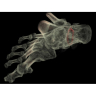

Травматология и ортопедия

• Диагностика сложных переломов и повреждений суставов.

• 3D-реконструкция костных структур для планирования операций.